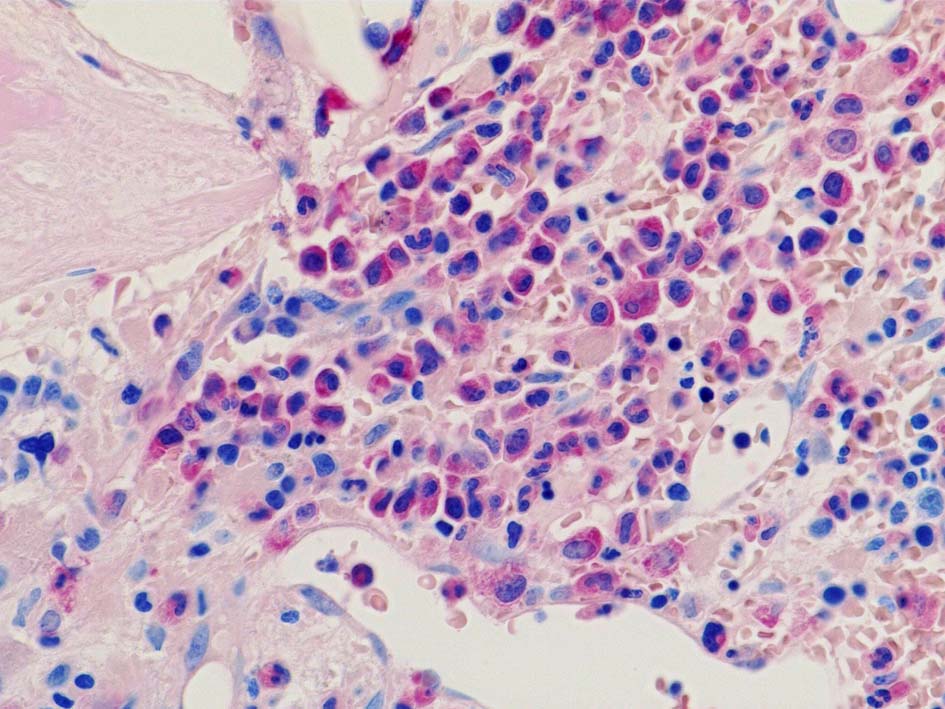

Case02; Meylofibrosis, overt fibrosis

77year-old female. 40歳時polycythemia veraと診断されていた.

[注] この症例は詳細は不明であるが, 過去にPVと診断されているため, PVに伴う二次性のmyelofibrosisの診断になる.

黒染する弾性線維の増生のほか, 赤く染まる膠原線維の増生が確認される. MF-2 fibrosis. 鍍銀染色の核染色をすると膠原線維の赤染がわからなくなるので行わない.